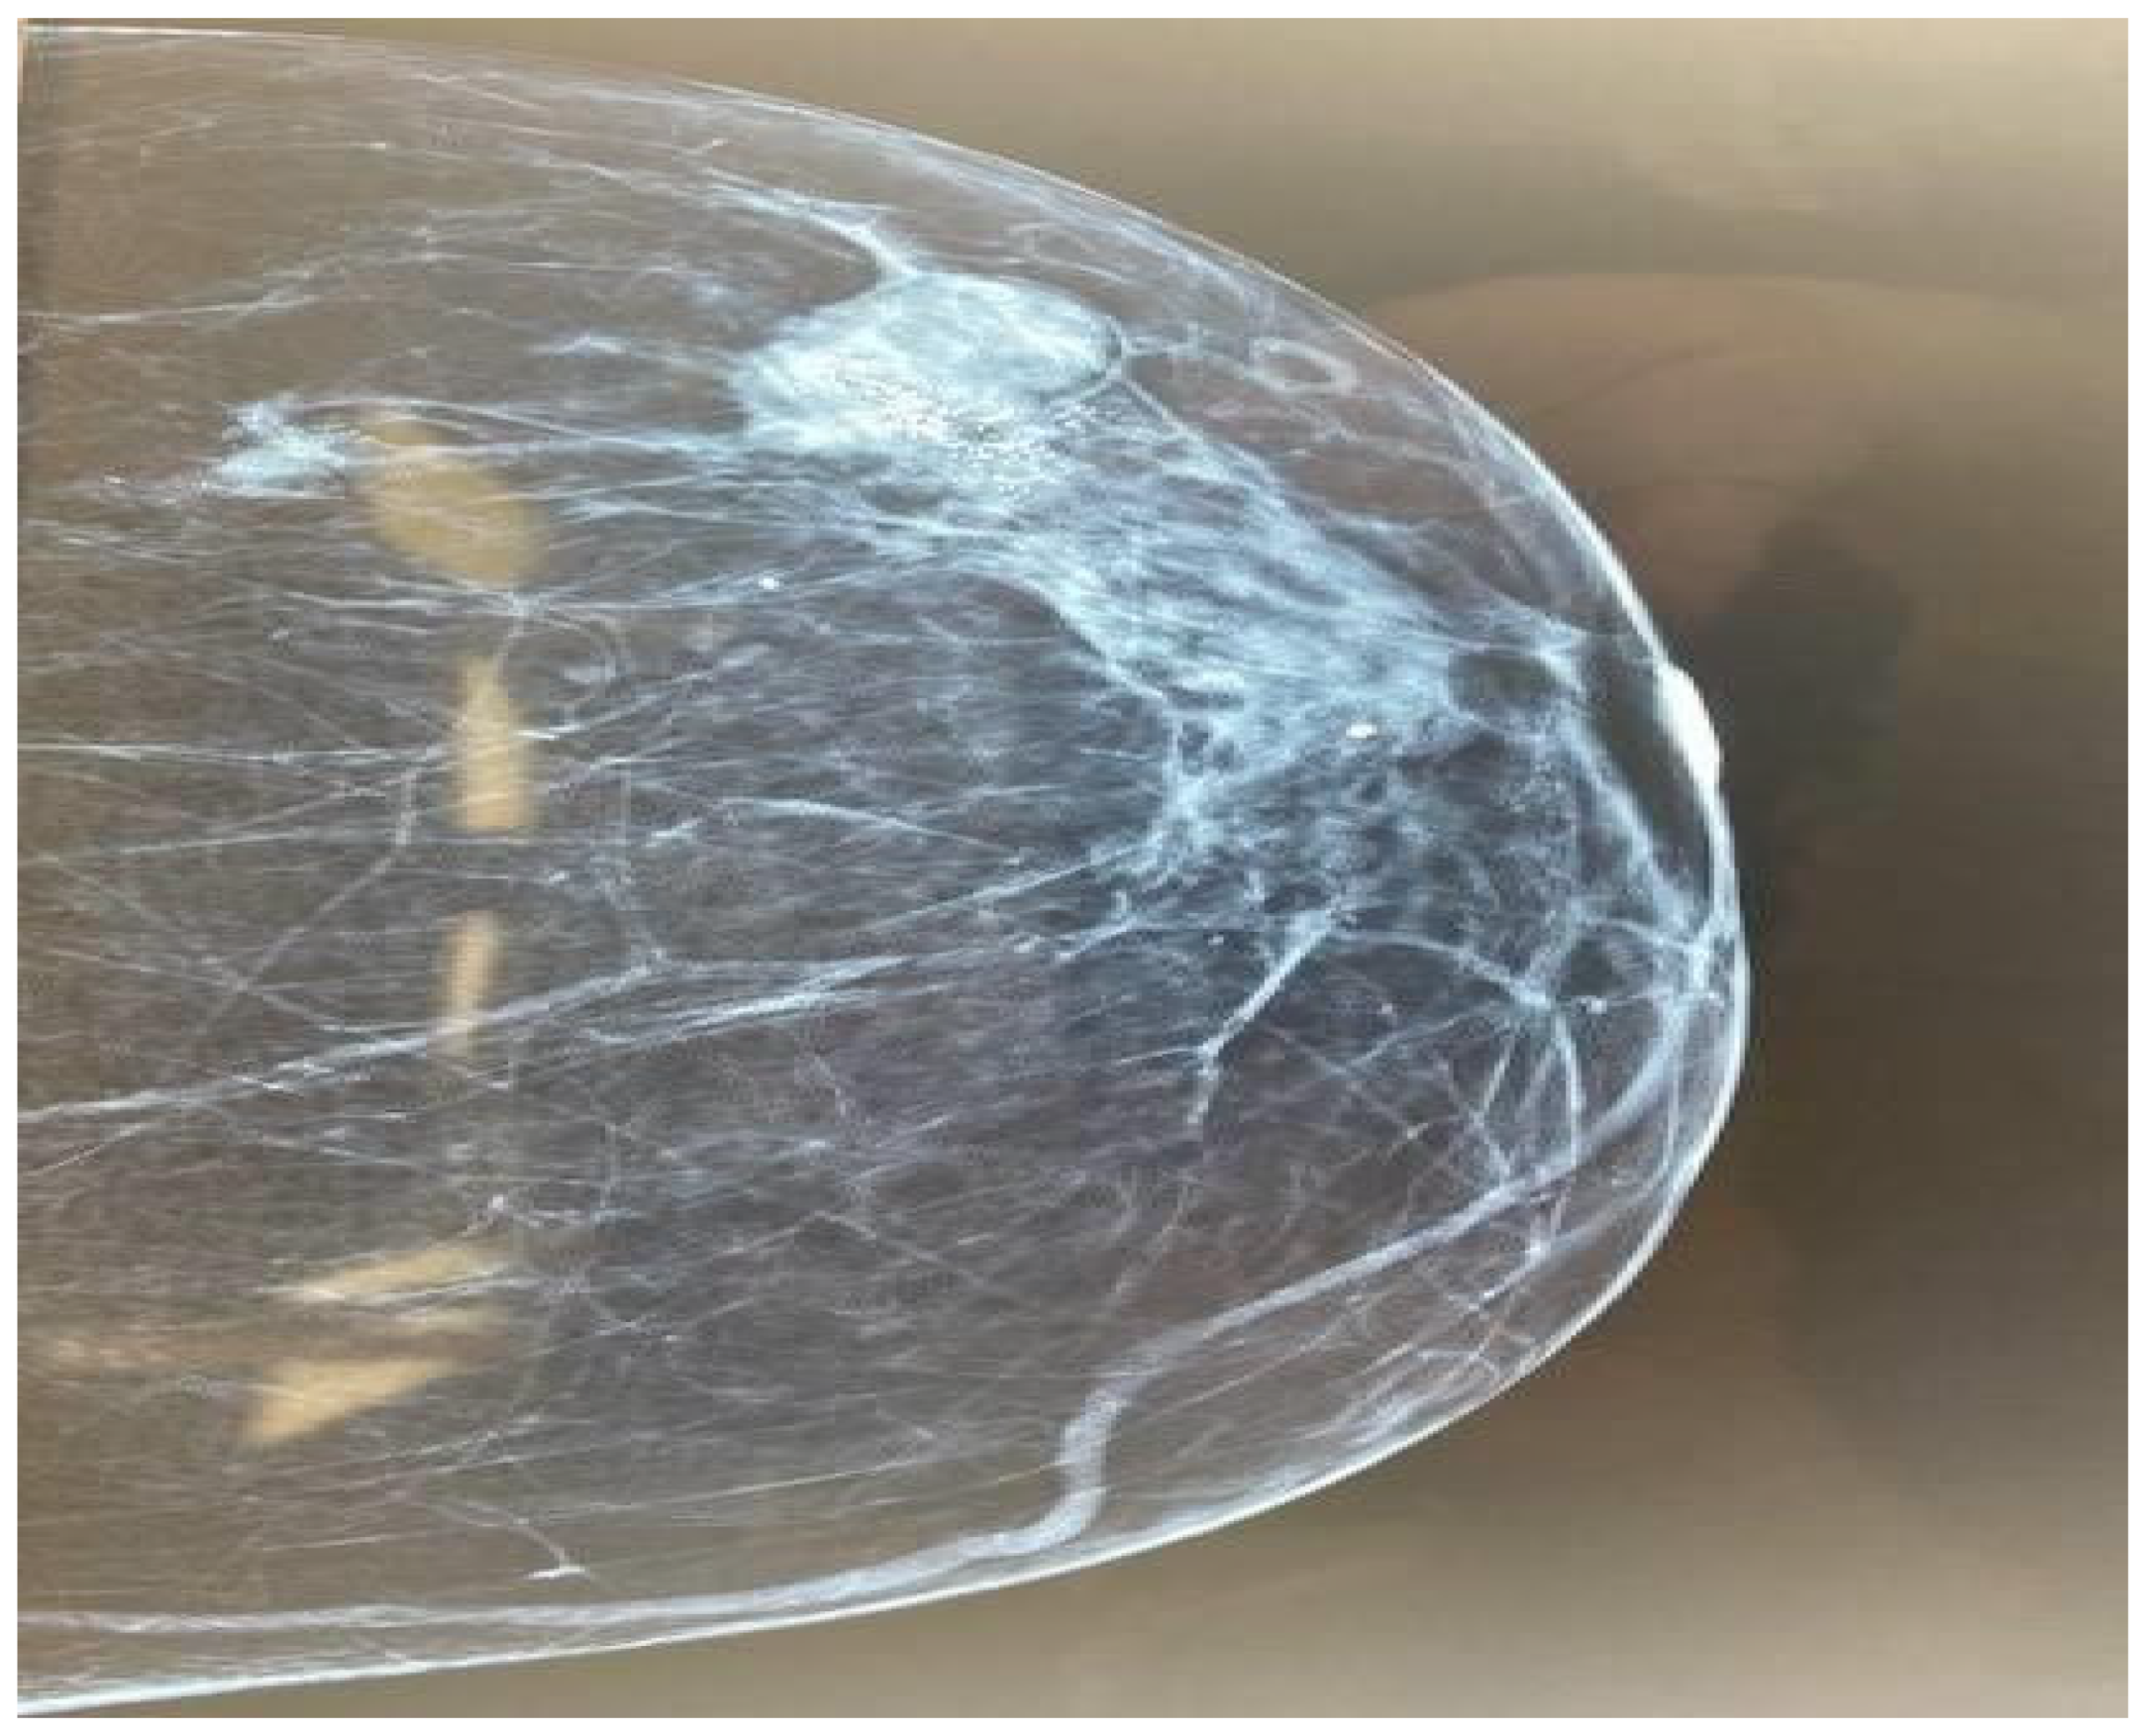

We highlight the case of a 66-year-old woman who presented at the outpatient breast department with an isolated nodule of the left breast. The clinical examination revealed a palpable breast lump between 3 and 5 o’clock. There were palpable left axillary lymph nodes. The patient mentions menarche at the age of 14 years old and menopause at the age of 53 years old. She had 2 full-term pregnancies, the first one at the age of 27, no history of miscarriage, and she had no history of hormonal contraception use. Other past medical history included asthma and osteopenia. The patient had mammography and breast ultrasound. These revealed two masses in the upper outer quadrant of the left breast, approximately 3 cm in diameter, one of which was characterized as BIRADS 5 (Figure 1). Two enlarged axillary lymph nodes were also found in the ipsilateral breast. Complete laboratory tests were performed, including tumor markers, the values of which were within normal limits. It was decided to proceed with surgical excision.

Figure 1. Mammography imaging of the left breast.